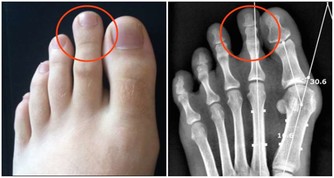

- 久居潮濕環境或陰雨或梅雨季 - 久坐或久站,缺少運動 - 常吃冰或過量食用生冷食物如生菜沙拉或寒性水果:西瓜、水梨、葡萄柚、橘子、奇異果 (偏寒濕) - 重口味如過鹹或過辣 (如辣椒、鹽巴、醬油、沙茶醬添加太多),例如常常在吃完麻辣火鍋之後,可以發現隔天早上雖然有排便,但是體重卻仍然上升 1~2 公斤,多半是因為重口味導致水分滯留 (偏濕熱) - 時常喝酒,過食肥甘厚味油膩之物 (偏濕熱) - 經前荷爾蒙改變,濕氣重體質的人容易經前下肢水腫 - 懷孕期間因為腹部血管、下腔靜脈受到子宮壓迫,容易造成血液回流狀況不佳,靜脈曲張,導致下肢容易腫脹;產後過補,吃太多種口味的食物,容易水分滯留體內,加上坐月子又很少運動中醫理論認為濕為陰邪,濕性重著黏膩妨礙氣機流通的特性,如果濕邪侵犯頭部,會出現頭部沉重疼痛,像戴了帽子或裹了濕毛巾;侵犯四肢,則會出現四肢酸重無力等症狀;侵犯腸胃,則會出現胃腸脹氣、腸鳴、食慾不振、大便稀軟或黏滯不暢,甚至水瀉等症狀;侵犯關節,則會出現關節腫脹疼痛等症狀;侵犯肌膚,則會出現皮下水腫、按之凹陷或皮膚濕疹起水泡等症狀。